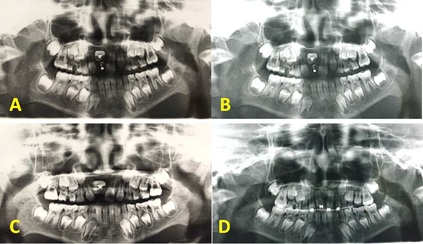

The apical foramen of impacted malformed central incisor was not closed, guided eruption combined with surgical exploration was possible. Lingual button was bonded on lingual side of the incisor during surgical flap operation. The patient was recalled after 1 week and orthodontic traction was taken. Removable appliances was used for 3 months. Interactive traction was used for 2 months. Fixed orthodontic treatment was planned to align the upper anterior teeth for 3 months (Figure 2). Lingual retainer was bonded from letaral incisor to letaral incisor (Figure 3).

Figure 2 (A to D): Panoramic radiography showing the movement of impacted dilacerated central incisor during orthodontic treatment.